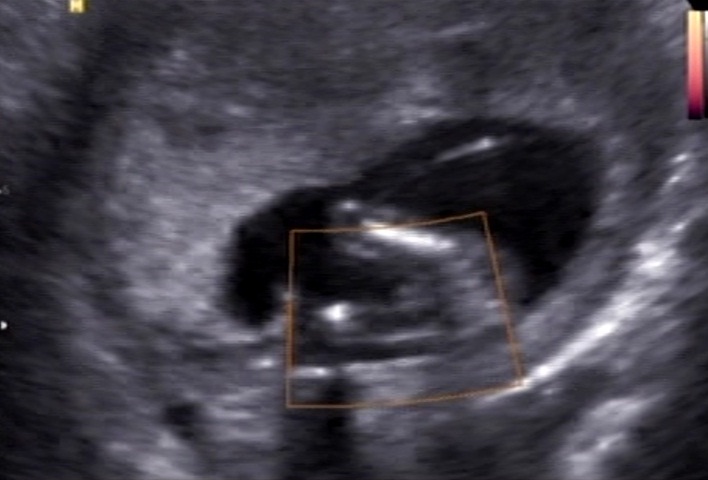

Boy or girl? 14 weeks.

Would you guess boy or girl? Could the white in the first pic be boy parts?

They are from a 14 week scan. Im having an other scan soon but im soo curios and would like to know what to expect when I go to that scan.

It seems to have something between the legs. My guess is a boy, hope this is what you want

Looks like there is something between the legs I would say boy.